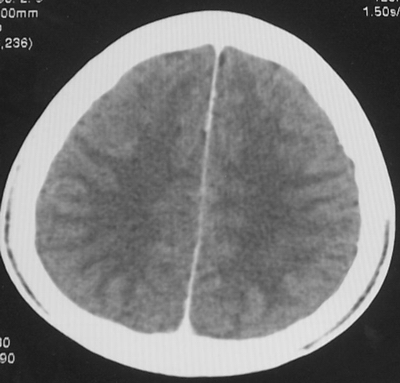

患者、男、18y,头痛5天入院。

左小脑、右丘脑区低密度影,无明显强化及占位表现,男18y,先考虑脑部炎性病变,如脑炎、血行播散性感染等,建议结合临床如脑脊液检验。

单独看左侧小脑半球的不规则形囊性低密度灶,从发病部位、年龄以及无强化、无占位效应的特点可以考虑毛细胞瘤型星形细胞瘤。同样,如果单独看右侧丘脑的近圆形低密度,也可以考虑囊变形星形细胞瘤。只是胶质细胞瘤一般为单发直接浸润、蔓延生长,而不是在脑内同时出现多个病灶,且瘤周没有一点儿水肿,暂时不予以考虑。

同时,现在已经进入冬天,一氧化碳中毒也需要考虑进去。不知道增强是什么时间做的,与平扫间隔几天?如果中间时间比较久而且进行吸氧等治疗,则平扫所示右侧颞叶密度比较低、右侧小脑半球以及脑桥也似有片囊状低密度,但在增强却没有发现就可以比较合理的解释了。